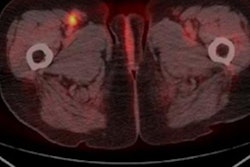

Complete metabolic response to therapy. A 72-year-old male with metastatic melanoma. Maximum intensity projection (MIP) of baseline (A) and transaxial fused (D) F-18 FDG-PET/CT images show a hypermetabolic right axillary lymph node (blue arrow), which is resolved on both first (B [MIP] and E [fused transaxial]) and second (C [MIP] and F [fused transaxial]) follow-up studies (green arrows). Image courtesy of the European Journal of Radiology.Results from baseline F-18 FDG-PET/CT scans showed uptake values (wSULmax and wSULpeak) as well as TBR parameters predicted three-year survival, and some of the TBR parameters predicted which patients survived after five years. Considerably more metabolic parameters extracted from the three- and six-month follow-up scans predicted three-year and five-year survival, the researchers stated.